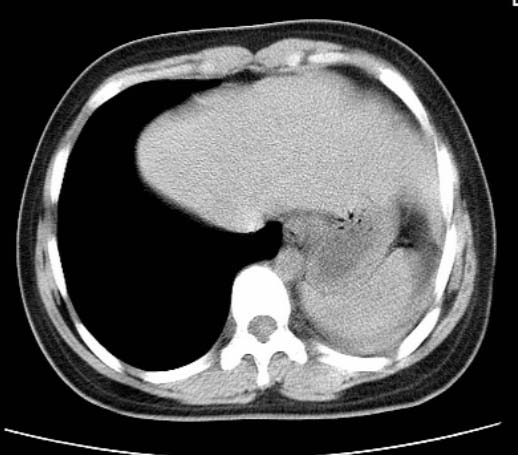

女  20岁。一月前咳血,诊“肺结核”抗痨治疗一月后,咳血停止,现复查。病人精神好。前后ct片对比未见明显变化。既往体检“正常”

1)考虑左肺结核并肺不张、支气管扩张。2)纵隔疝。

以前体检正常只能考虑左肺结核并肺不张、支气管扩张。2)纵隔疝。

考虑左肺结核,左肺毁损,纵膈左偏,既往体检正常不可靠,tb一个月也不会这个样子的,有钙化,应该病程较长,冰冻三尺非一日之寒!

考虑左肺结核,左肺毁损,纵膈左偏,既往体检正常不可靠,tb一个月也不会这个样子的,有钙化,应该病程较长,冰冻三尺非一日之寒